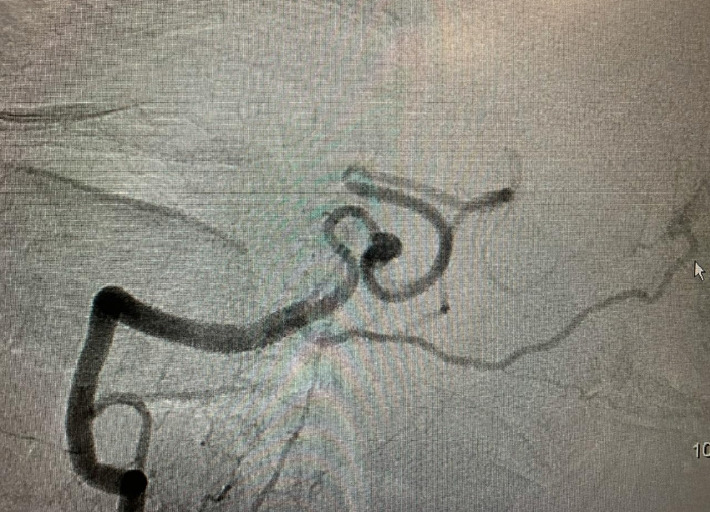

小脑后下动脉(PICA)夹层动脉瘤是一种不常见的病变。其解剖结构和夹层位置各不相同,但通常发生在小脑后下动脉的起源部位。夹层的 PICA 动脉瘤通常无血管形态,涉及整个动脉段,无法切开。尽管如此,近年来这类血管性病变的发现率有所上升,因此有必要对其进行识别,并采取适当的处理方式。在本报告中,我们描述了一例 73 岁的男性患者,他有严重的头痛病史,伴有颈部僵硬、恶心、呕吐、头晕、活动不足、精神错乱和行走困难。通过脑计算机断层扫描(CT)进行的放射学检查显示,髓质前和桥脑前海绵体有轻微出血,脑血管造影显示有一个剥脱性 PICA 动脉瘤。尽管治疗难度很大,但患者还是选择了显微手术治疗。手术在 P2/3 节段之间进行了端对端吻合,临床和影像学效果良好。我们讨论了这个不寻常的病例,回顾了有关临床表现、PICA 夹层动脉瘤血管造影特点的现有文献,并评估了接受显微手术治疗的患者的临床和血管造影结果。

Dissecting posterior inferior cerebellar artery (PICA) aneurysms are uncommon lesions. Their anatomy and the location of the dissection are variable, however, they usually occurs at the origin of the PICA. Dissecting PICA aneurysms generally have non-vascular morphology involving an entire segment of the artery and cannot be cut. Nevertheless, the detection of these vascular lesions has increased latterly, so it is necessary to recognize it and take the appropriate management modalities for these injuries. In this report, we describe a case of a 73-year-old male patient, who presented a history of severe headache, associated with neck stiffness, nausea, vomiting, dizziness, hypoactivity, mental confusion, and walking difficulty. Radiographic investigation with brain computed tomography (CT) showed mild bleeding in a pre-medullary and pre-pontine cistern, and cerebral angiogram showed a dissecting PICA aneurysm. Despite being a challenging treatment, microsurgery management was the chosen modality. It was performed an end-to-end anastomosis between the p2/p3 segments, showing to be effective with good clinical and radiographic outcomes. We discussed an unusual case, reviewing the current literature on clinical presentations, the angiographic characteristics of the dissecting aneurysms of PICA, and evaluating the clinical and angiographic results of patients undergoing microsurgical treatment.